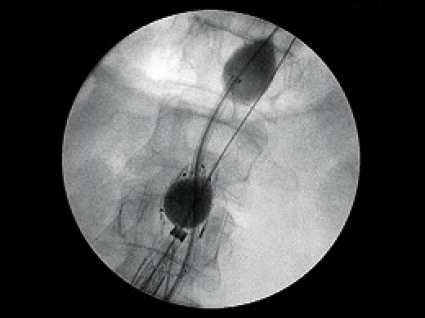

Kontroll av blödningen under hela stentgraftinläggningen kunde i 73 procent (11/15 patienter) genomföras med ocklusionsballong, initialt ovanför visceral- och njurartäravgångarna och därefter distalt om njurartärerna. Operationsproceduren innefattade en sekvens, där två uppblåsta ocklusionsballonger var på plats (Figur 1). Operationen avslutades med en kontrollangiografi för att avgöra om aneurysmet var exkluderat och om kvarstående läckage förekom.